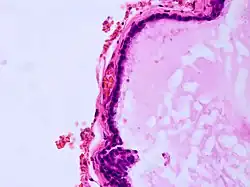

Als Kolloidzyste wird eine gutartige zystische Struktur bezeichnet, die typischerweise im Bereich des dritten Hirnventrikels auftritt.[1] Kolloidzysten können das Foramen Monroi verlegen, was zu einem Liquoraufstau mit Hydrozephalus führt. Symptomatische Kolloidzysten werden neurochirurgisch häufig minimalinvasiv neuroendoskopisch entfernt. Bei asymptomatischen (beschwerdefreien) Kolloidzysten, bei denen es sich nicht selten um Zufallsbefunde handelt, kann die Operationsindikation erwogen werden, wenn die Größe geeignet erscheint, das Foramen Monroi zu verlegen. Plötzliche Todesfälle in Zusammenhang mit vorher asymptomatischen Kolloidzysten sind in Einzelfällen beschrieben worden.[2]